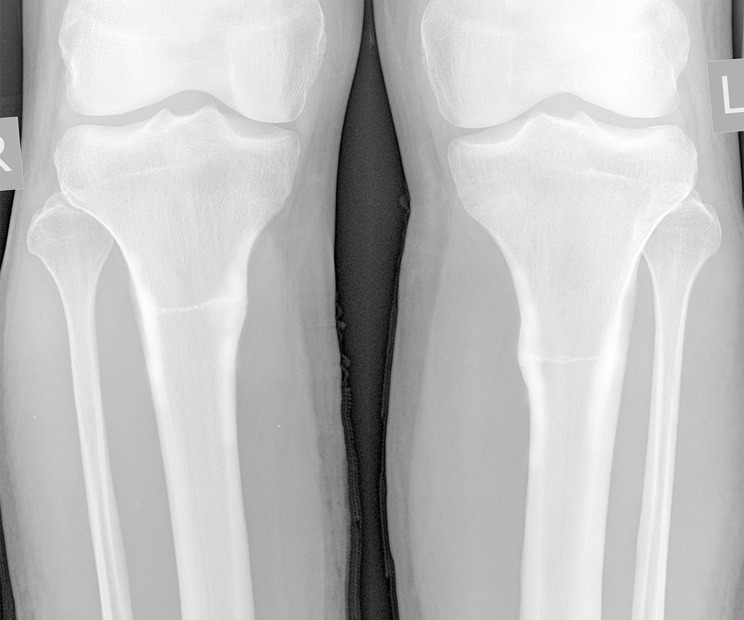

Aim: To familiarize specialists with the possibility of simultaneous bilateral stress fractures of amputation residual limbs resulting from intensive loads and poor-quality prosthetics causing chronic compartment syndrome. A case of bilateral stress fractures of the tibia in a 28-year-old male military serviceman with paired transtibial amputation is presented. The fractures occurred in the process of active exploration of poorly fitting prostheses, complicated by chronic compartment syndrome that masked the clinical picture.

Techniques: Radiography, ultrasound, blood biochemistry, measurement of subfascial pressure.

Conclusion: With complaints from the patient with an amputation stump of muscle and bone pain that appeared after exercise, passed after rest, and reparative reaction detected on radiographs, functional overstrain of the bone should be suspected, which can potentially lead to a stress fracture. The causes of stress fractures in the patient were acute overstrain of the bone tissue during prosthesis development, noncompliance with the loading and resting regimes, and local disturbance of the bone blood supply due to the narrowed rigid socket of the prosthesis. Stress fractures of the bone tissue of the amputation stump contain elements of insufficiency and fatigue. Chronic compartment syndrome may exacerbate and mask the stress fracture.